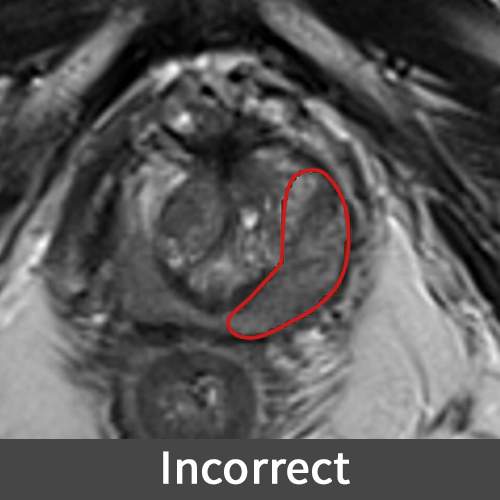

Prostate Biopsy

Regions of Interest (ROIs) are marked on prostate medical images to define areas that may need be biopsied for cancer evaluation. These ROIs guide a robotic system to accurately direct the biopsy needle to the targeted tissue within the prostate. The tissue samples collected are then examined and guide subsequent treatment planning for the patient.

In this example, a ROI for a prostate biopsy is inaccurately marked. If this error passes undetected, it may result in the sampling of an incorrect area, potentially resulting in misdiagnosis.

Figure B (Right): An incorrect and correct contours of a prostate lesion.